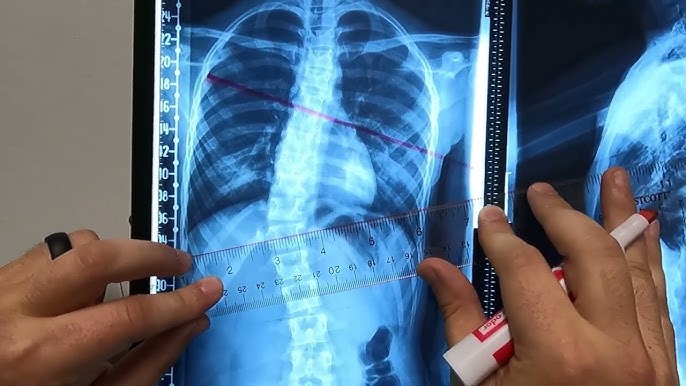

لماذا تختلف زاوية كوب بين مراكز الأشعة والطبيب؟ وكيف يؤثر ذلك على متابعة حزام اعوجاج العمود الفقري؟ عندما يبدأ الطفل أو المراهق رحلة علاج اعوجاج العمود الفقري باستخدام الحزام الطبي، يصبح سؤال الأهل الأهم